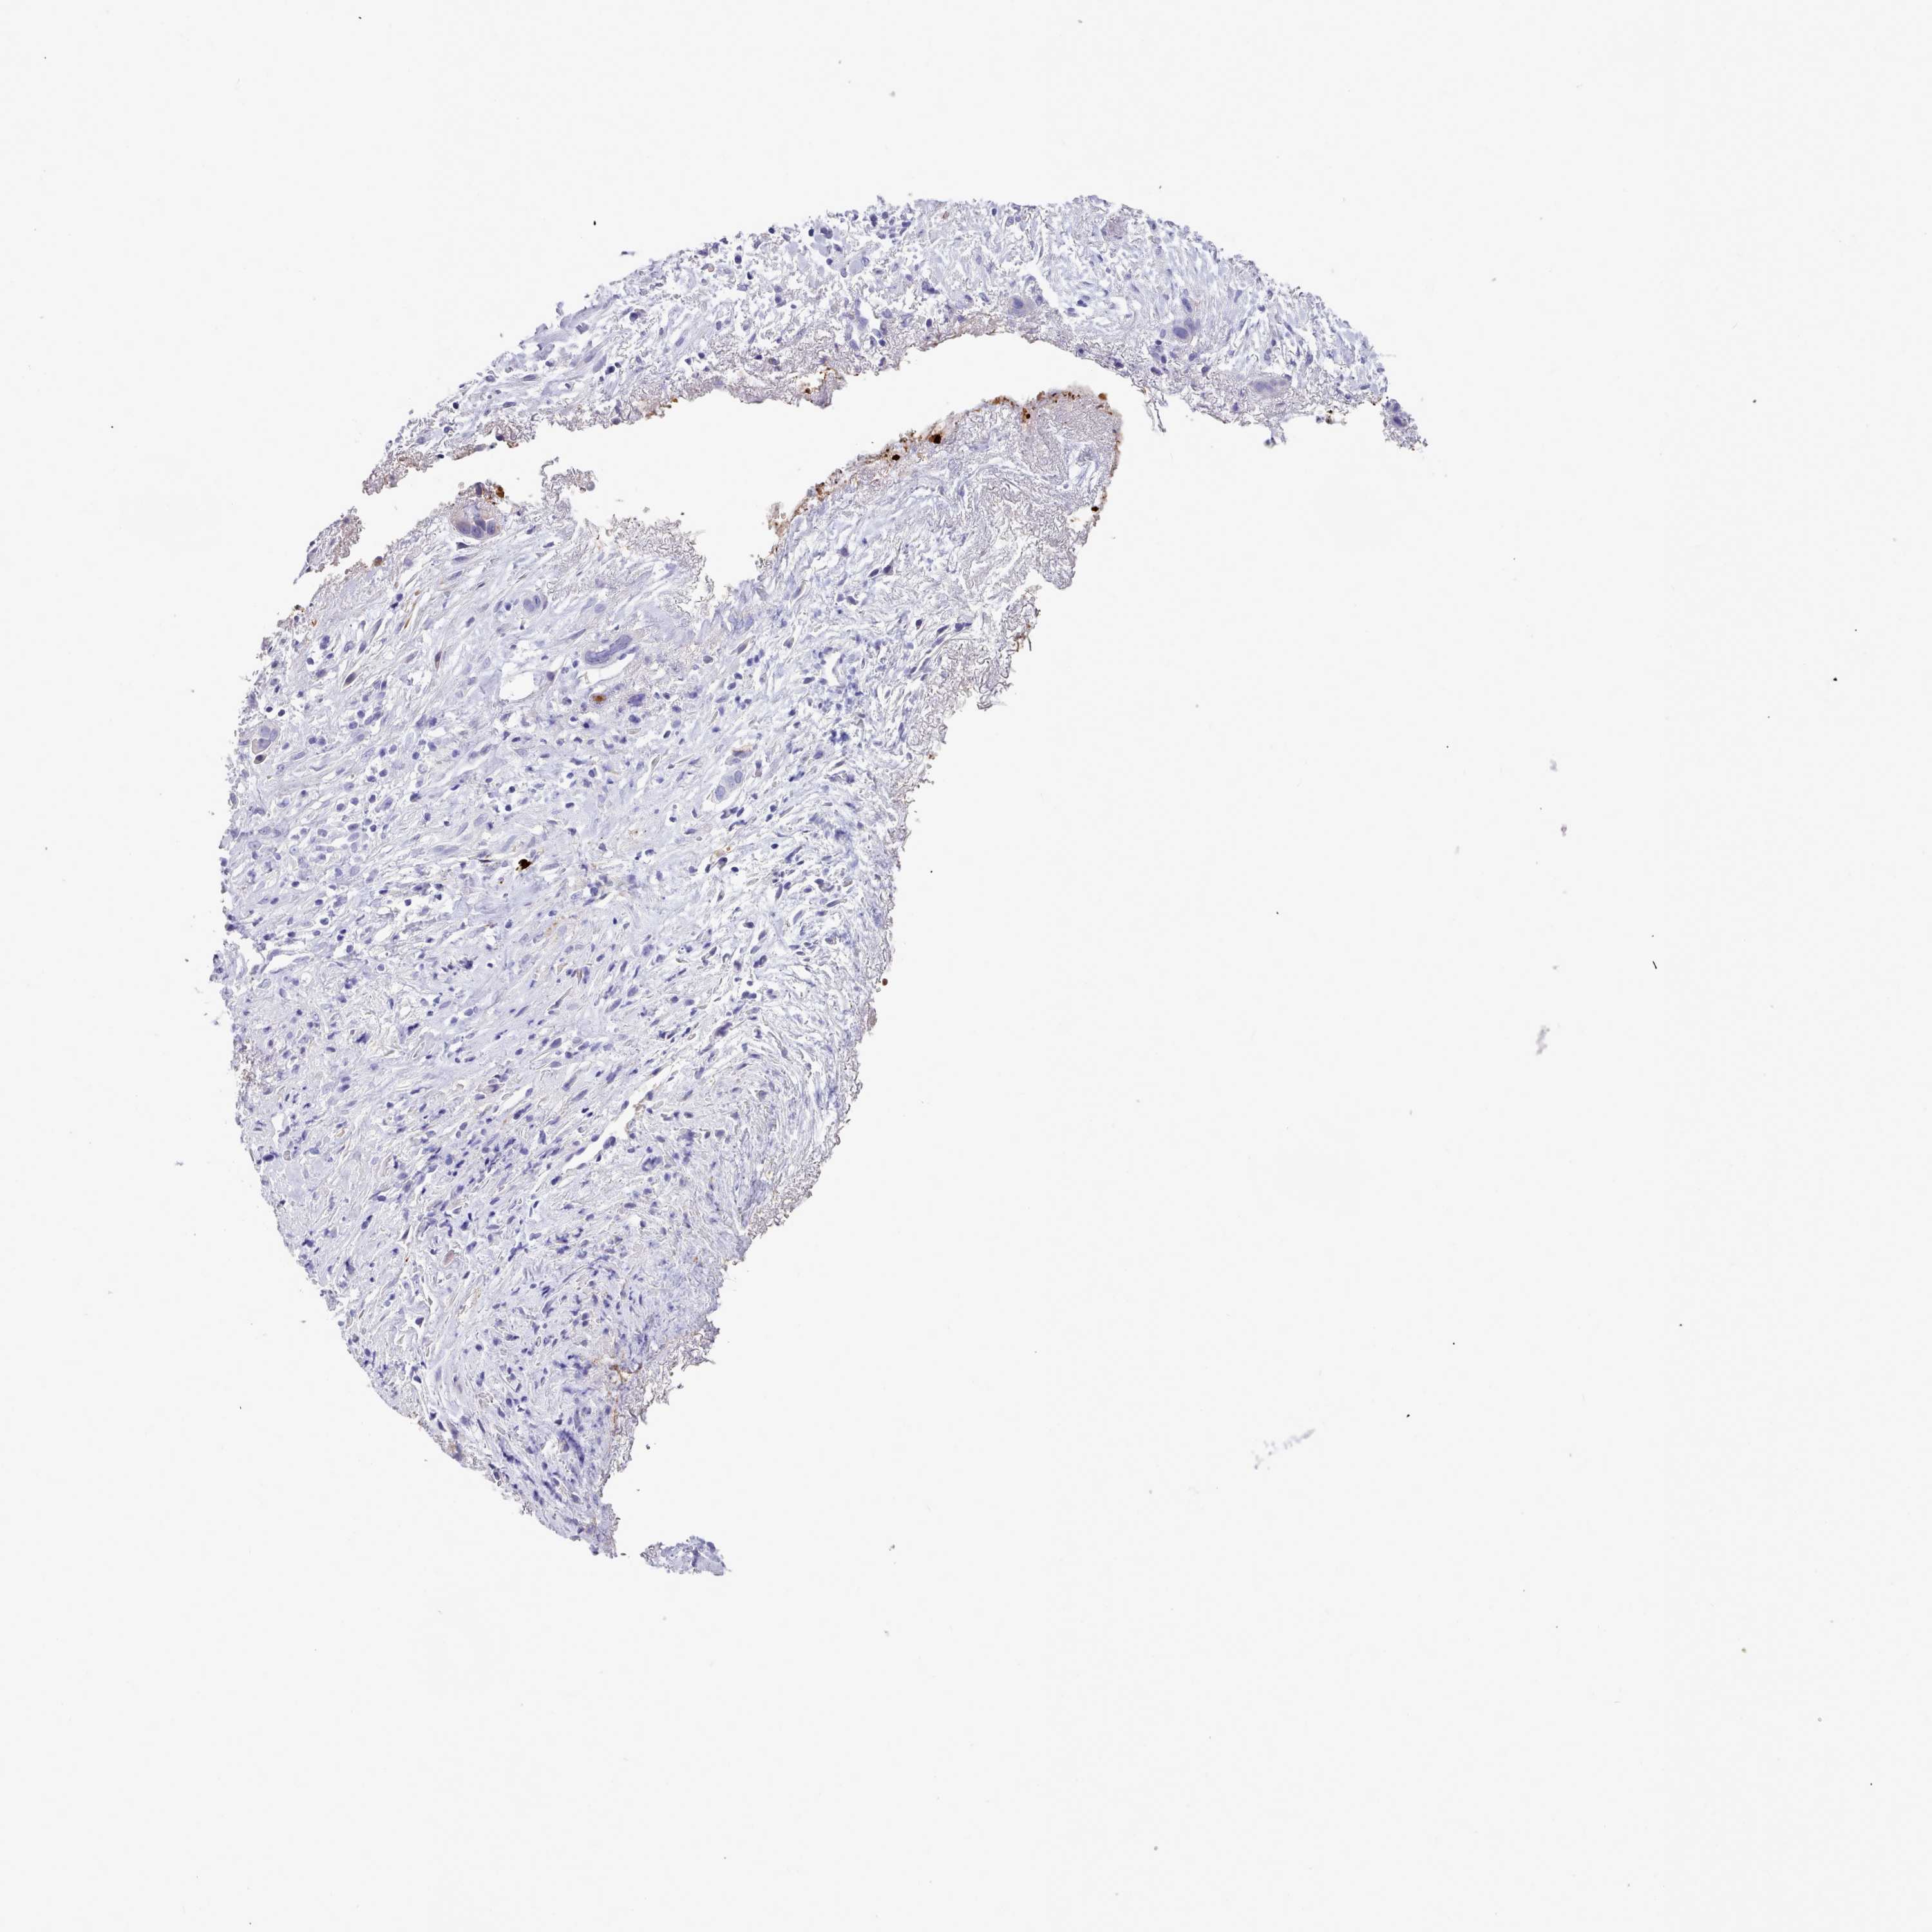

LIVER CANCER - Protein expressioni

A mouse-over function shows sample information and annotation data. Click on an image to view it in a full screen mode. Samples can be filtered based on level of antibody staining by selecting one or several of the following categories: high, medium, low and not detected. The assay and annotation is described here.

Note that samples used for immunohistochemistry by the Human Protein Atlas do not correspond to samples in the TCGA dataset.

Antibody stainingi

Antibody staining in the annotated cell types in the current human tissue is reported as not detected, low, medium, or high, based on conventional immunohistochemistry profiling in selected tissues. This score is based on the combination of the staining intensity and fraction of stained cells.

Each image is clickable and will lead to virtual microscopy that enables deeper exploration of all samples and also displays staining intensity scores, fraction scores and subcellular localization as well as patient and tissue information for each sample.

Antibody HPA029367

Staining

High

Medium

Low

Not detected

Intensity

Strong

Moderate

Weak

Negative

Quantity

>75%

75%-25%

<25%

None

Location

Nuclear

Cytoplasmic/membranous

Cytoplasmic/membranous,nuclear

Cholangiocarcinoma

Carcinoma, Hepatocellular, NOS